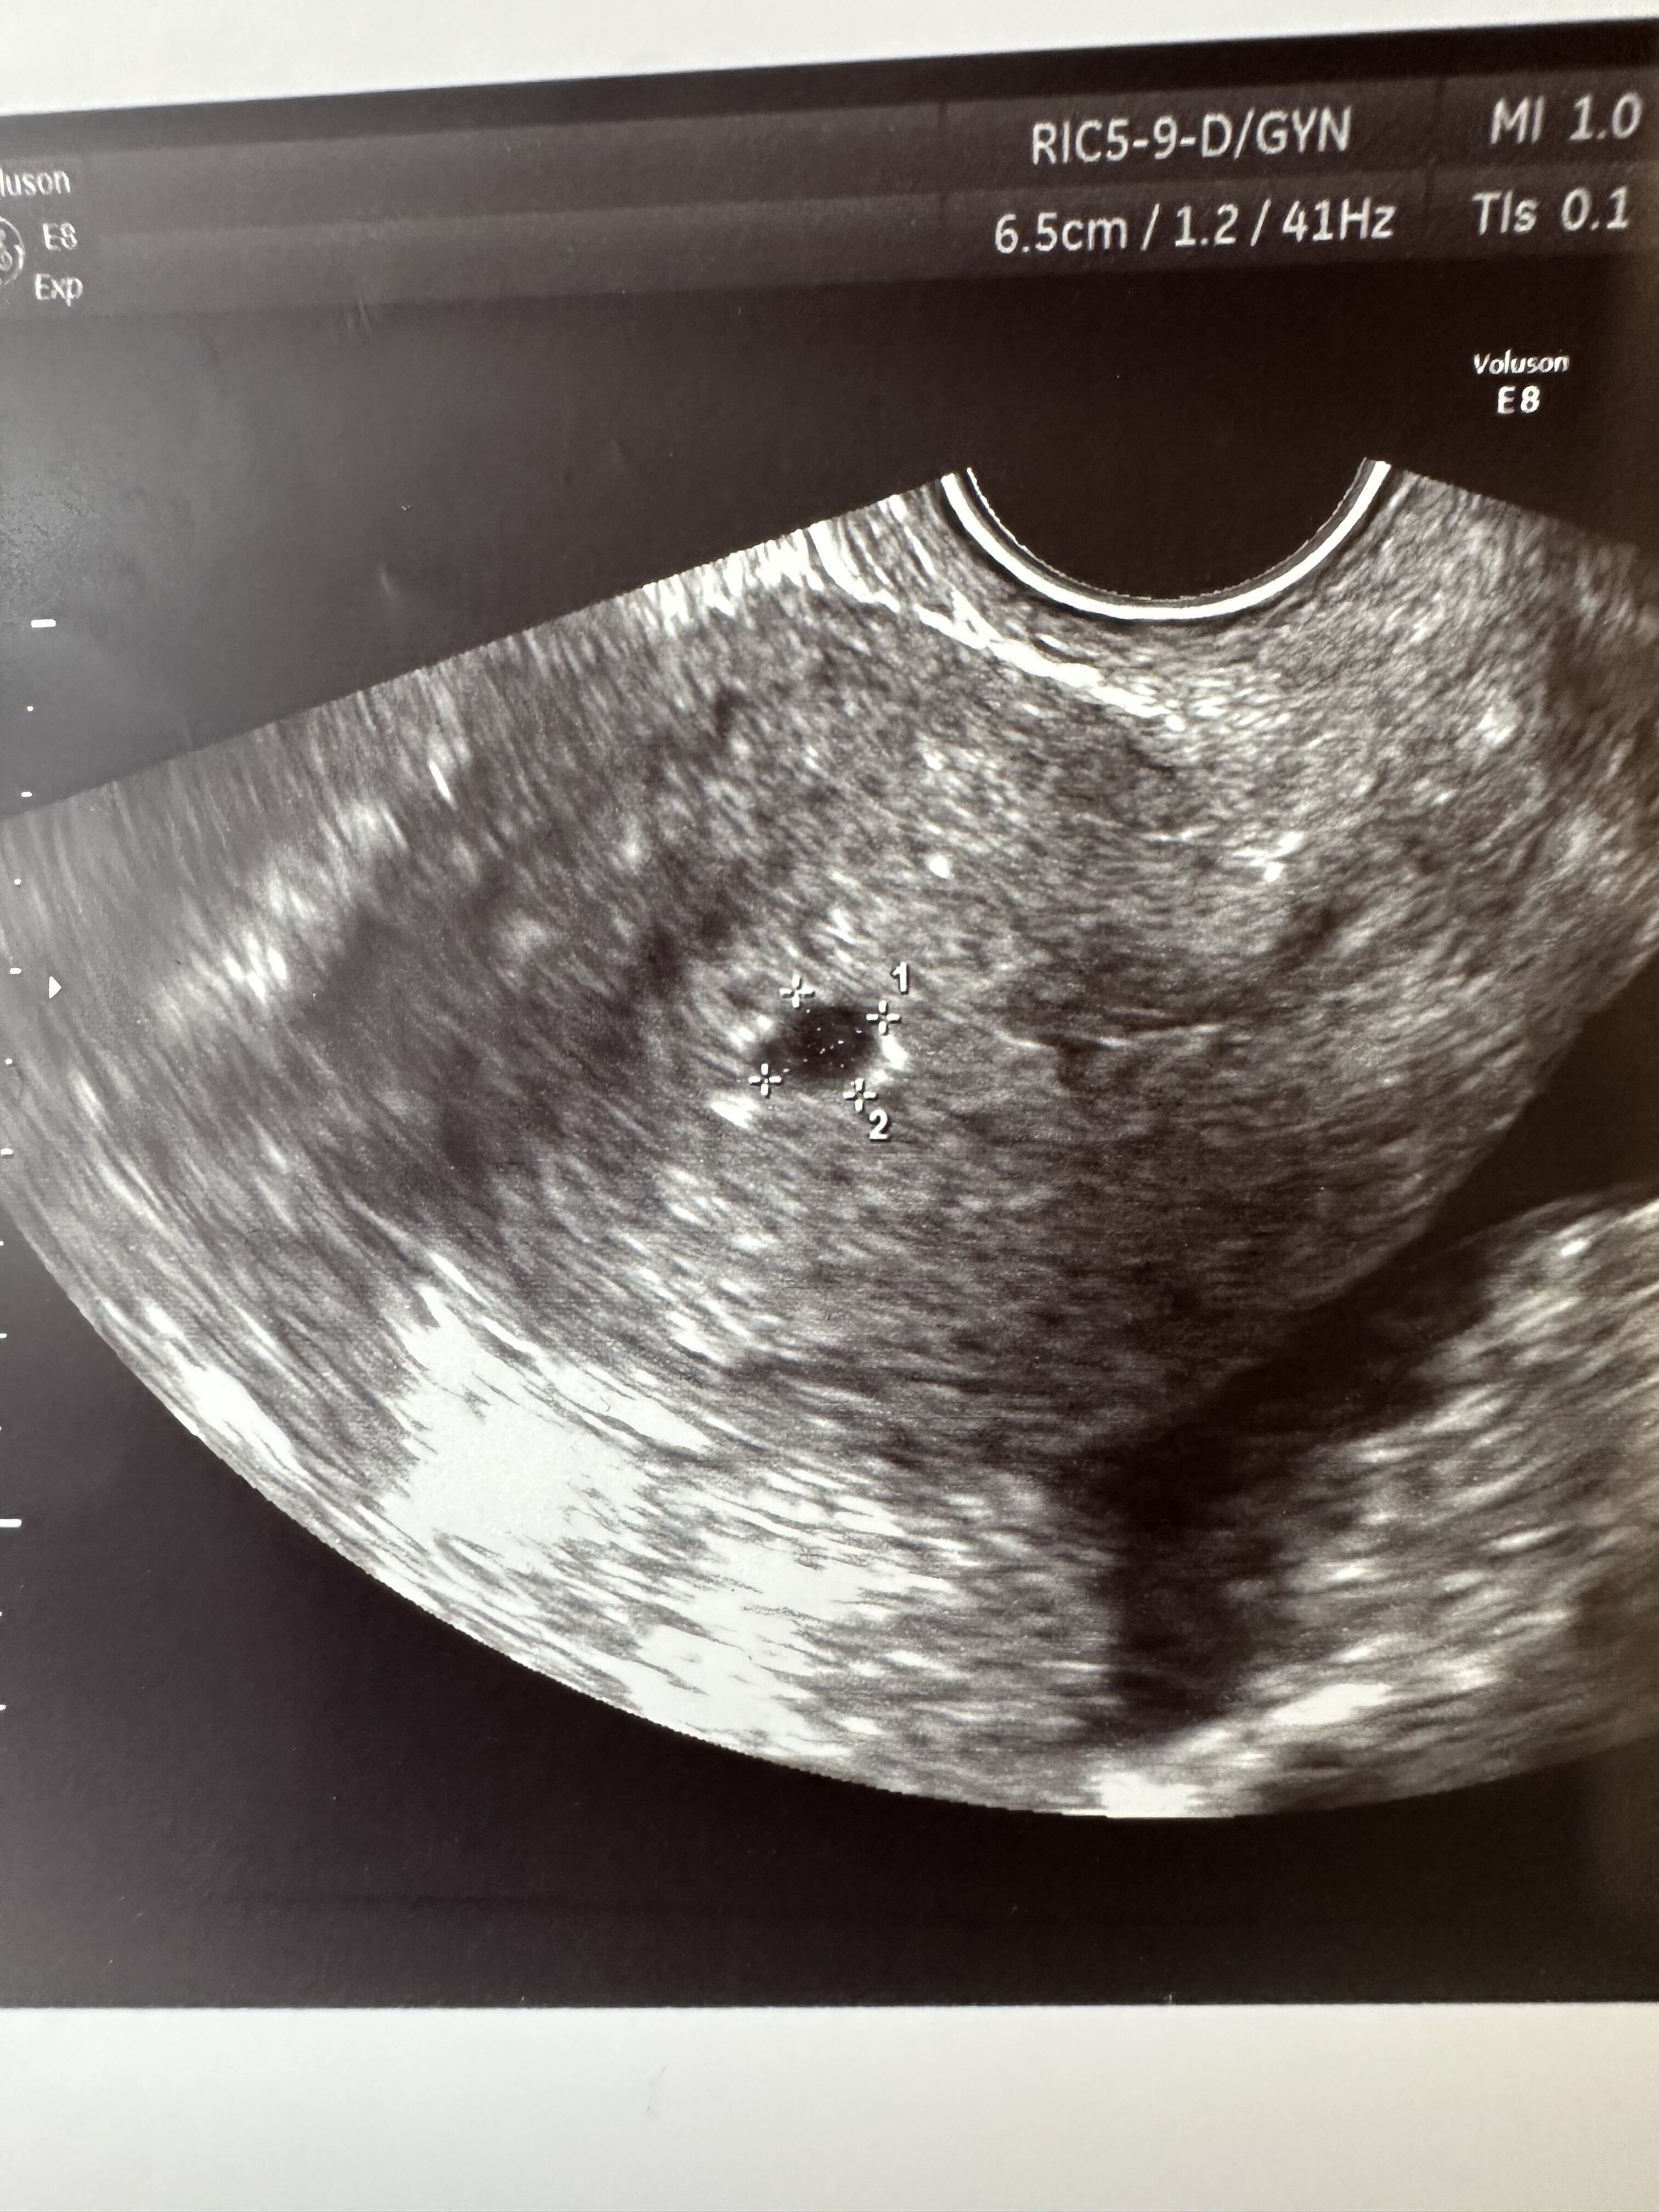

Dziewczyny możecie mi napisać wymiary waszego pęcherzyka żółtkowego - YS?

Przez na początku ciąży miałam tylko informację że pęcherzyk ciążowy jest w macicy - bez wymiarów. Potem mierzono już tylko długość zarodka.

A jaki miałaś na tej 1 wizycie wymiar?

Załączniki

• IMG_5140.jpeg

IMG_5140.jpeg

1,4 MB · Wyświetleń: 107